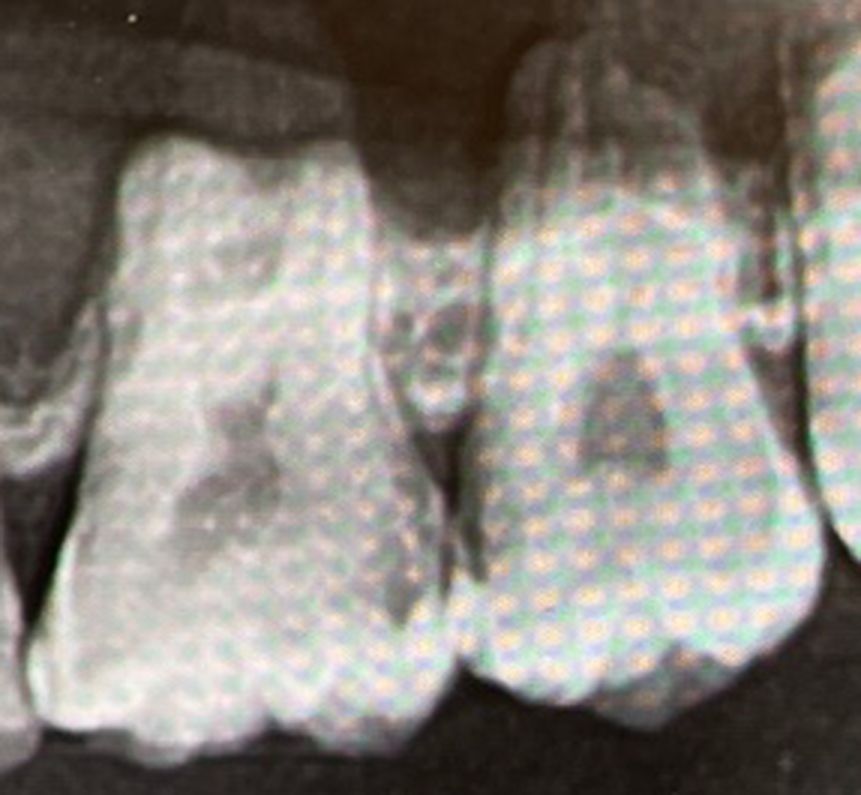

현재 3곳 신경치료 진행하였으며, 위의 사진위치는 16, 17번 어금니입니다.

하지만 치경으로 보았을때 속에서 검은색이 비쳐보이는것을 보고는 충치인것을 확인해

찍은 사진인데 많이 심하게 썩었네요...혹시 신경치료 해야될까요? ㅜㅜ

보이는 부위의 충치가 심합니다. 사진 상으로는 신경까지 근접하지 않은 것처럼 보일 수 있지만 3차원적으로 고려했을 때 충치 제거 과정에서 치수가 노출될 가능성이 큽니다. 또한 치수가 노출되지 않더라도 너무 가까워서 그대로 치료하게 되면 시린 증상 등이 나타날 수 있어 신경치료를 할 가능성이 매우 높습니다. 물론 치료를 들어가봐야 정확한 것은 판단할 수 있습니다.

사진으로 봤을 경우에 인접면에 충치가 많이 진행되어 있는것으로 보입니다.

충치의 범위는 사진으로 보이는것보다 크게 있는 경우가 많기 때문에 충치를 제거하다가 신경이 노출된다면 신경치료가 필요할수 있습니다.

치아 사이가 많이 썩으신거 같아 보이네요. 범위는 넓지 않지만 썩은 부위가 좋지 않아서 신경치료 가능성이 있어 보입니다.